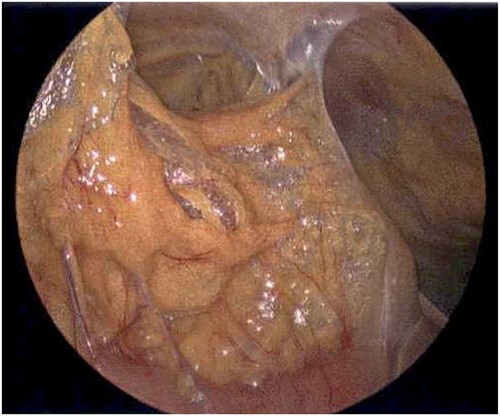

On Hospital Day 2, an interval CXR showed continued resolution of the right-sided pneumothorax but worsening subcutaneous emphysema of the bilateral chest wall and pneumoperitoneum (Fig. 3). Surgical consultation was sought, leading to diagnostic laparoscopy. In the abdomen, emphysematous changes within the gastrohepatic ligament and omental adhesions to the anterior abdominal wall were visualized (Figs 5 and 6). Laparoscopic exploration revealed no diaphragmatic injury or perforated viscera but identified emphysematous changes throughout the preperitoneal space, small and large bowel mesentery, and right paracolic gutter (Figs 7 and 8). Immediate post-op CXR no longer showed evidence of pneumoperitoneum (Fig. 4). The patient was transferred back to the ICU and extubated after three days on Day 5. After the removal of chest tube and transfer to a medical floor on Day 8, the patient developed aspiration pneumonia that was treated with antibiotics. She was discharged on Day 15.

Laparoscope of the anterior abdominal wall revealing emphysematous changes within the preperitoneal space.